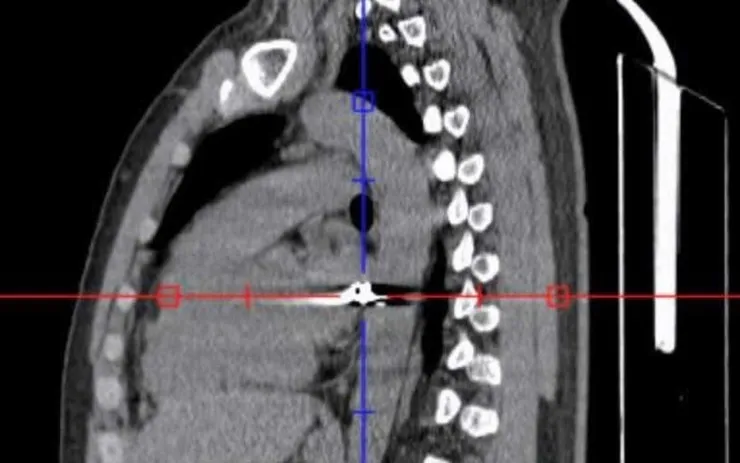

Qua thăm khám ban đầu, các bác sĩ xác định viên đạn đi theo đường phức tạp từ vùng lưng phải xuyên qua lồng ngực sang bên trái - khu vực tập trung nhiều cơ quan trọng yếu như tim, phổi và các mạch máu lớn, đe dọa trực tiếp đến tính mạng.

Sau hơn 4 giờ phẫu thuật căng thẳng, ekip đã kiểm soát được tổn thương, đồng thời gắp thành công một đầu đạn kích thước khoảng 0,3 x 0,5cm ra khỏi cơ thể người bệnh.